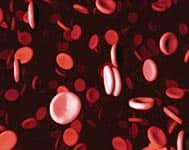

Bridge Three: Nanotechnology—Evolution in MotionEven Kurzweil acknowledges that his “third bridge”—the advent of nanotechnology—is “very futuristic.” However, having spent much of his life studying the rate of technological innovation, he is convinced that nanotechnology is the future. “It sounds very futuristic, but I’d point out there are already many experiments in animals that use blood cell-sized devices,” he explains. “One experiment we write about in the book involves a device the size of a blood cell that cured type I diabetes in rats. Pancreatic islet cells are actually inside the device. Glucose gets into the islet cells to be measured and insulin is released. It works perfectly normally. That’s occurring today.”

Kurzweil predicts a future in which these tiny robots are everywhere, attacking a host of conditions and enabling humans to “go substantially beyond the limitations of biology.” Robots the size of red blood cells could be injected by the billions to carry oxygen more efficiently than can actual red blood cells. Neurons could be enhanced by tiny microcomputers implanted in the capillaries of the brain, which would communicate with biological cells, each other, and a wireless Internet. Still other robots could monitor our blood glucose and maintain a safe level of insulin, rendering diabetes powerless. The opportunities are endless. “We’ll be able to provide full-immersion virtual reality from within the central nervous system,” he says. “‘Nanobots’ could shut down the signals coming from your real nervous system and put in place signals you would be receiving if you were in the virtual environment. Designing new virtual environments will be a new art form.” This concept strikes to the very heart of what it means to be human. To many, the idea of tiny robots working within our bodies is literally heresy, evoking images of horror movies and a world populated by cyborg beings that have lost their essential humanity. Once again, however, Kurzweil has no patience for this critique. This fear will be swept away, he says, by the enormous benefits associated with this technology. He points out that the miniaturization of technology is already increasing exponentially. Computers that once required whole rooms to operate now fit within the palm of a hand. It is only a matter of time before they can fit within the walls of human arteries. “We will become our technology,” he says. “We’re going to merge with it and will be indistinguishable from it. It’s not going to be a matter of how we compete with the machines. We will become the machines.”